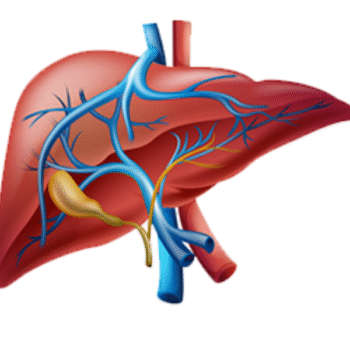

Liver Function Test (LFT) – Comprehensive Panel

₹549.00Original price was: ₹549.00.₹499.00Current price is: ₹499.00.Book NowSample Type: Serum (Blood Sample)

Fasting Required: Not mandatory (preferred 2–3 hrs post last meal)

Reporting Time: 24 hours

Lab Visit :- Available Home Collection :- Available -